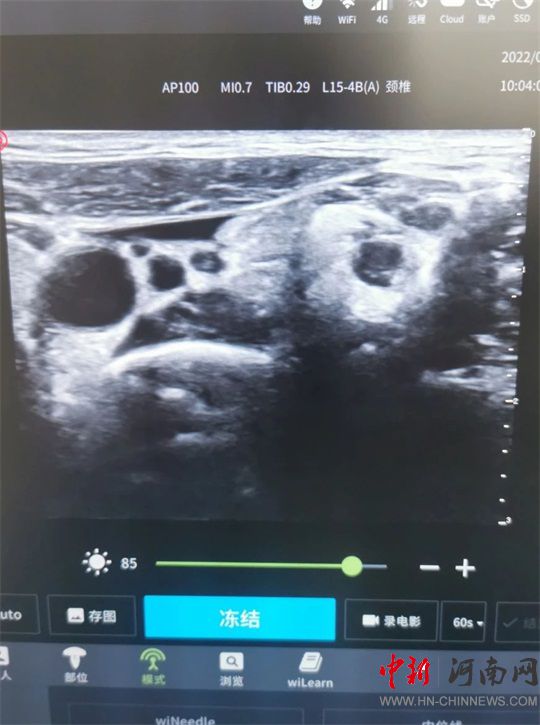

并進(jìn)行超聲引導(dǎo)下

星狀神經(jīng)節(jié)阻滯治療

通過超聲定位

頸6椎體橫突

穿刺針避開神經(jīng)、血管

抵達(dá)頸動(dòng)脈鞘外

注入藥液

治療完成